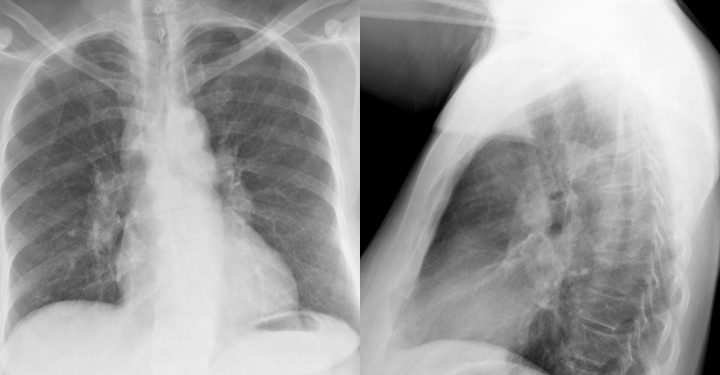

Gallery Sarcoid Sarcoid Case 5 PA & Lat

Case 5 PA & Lat